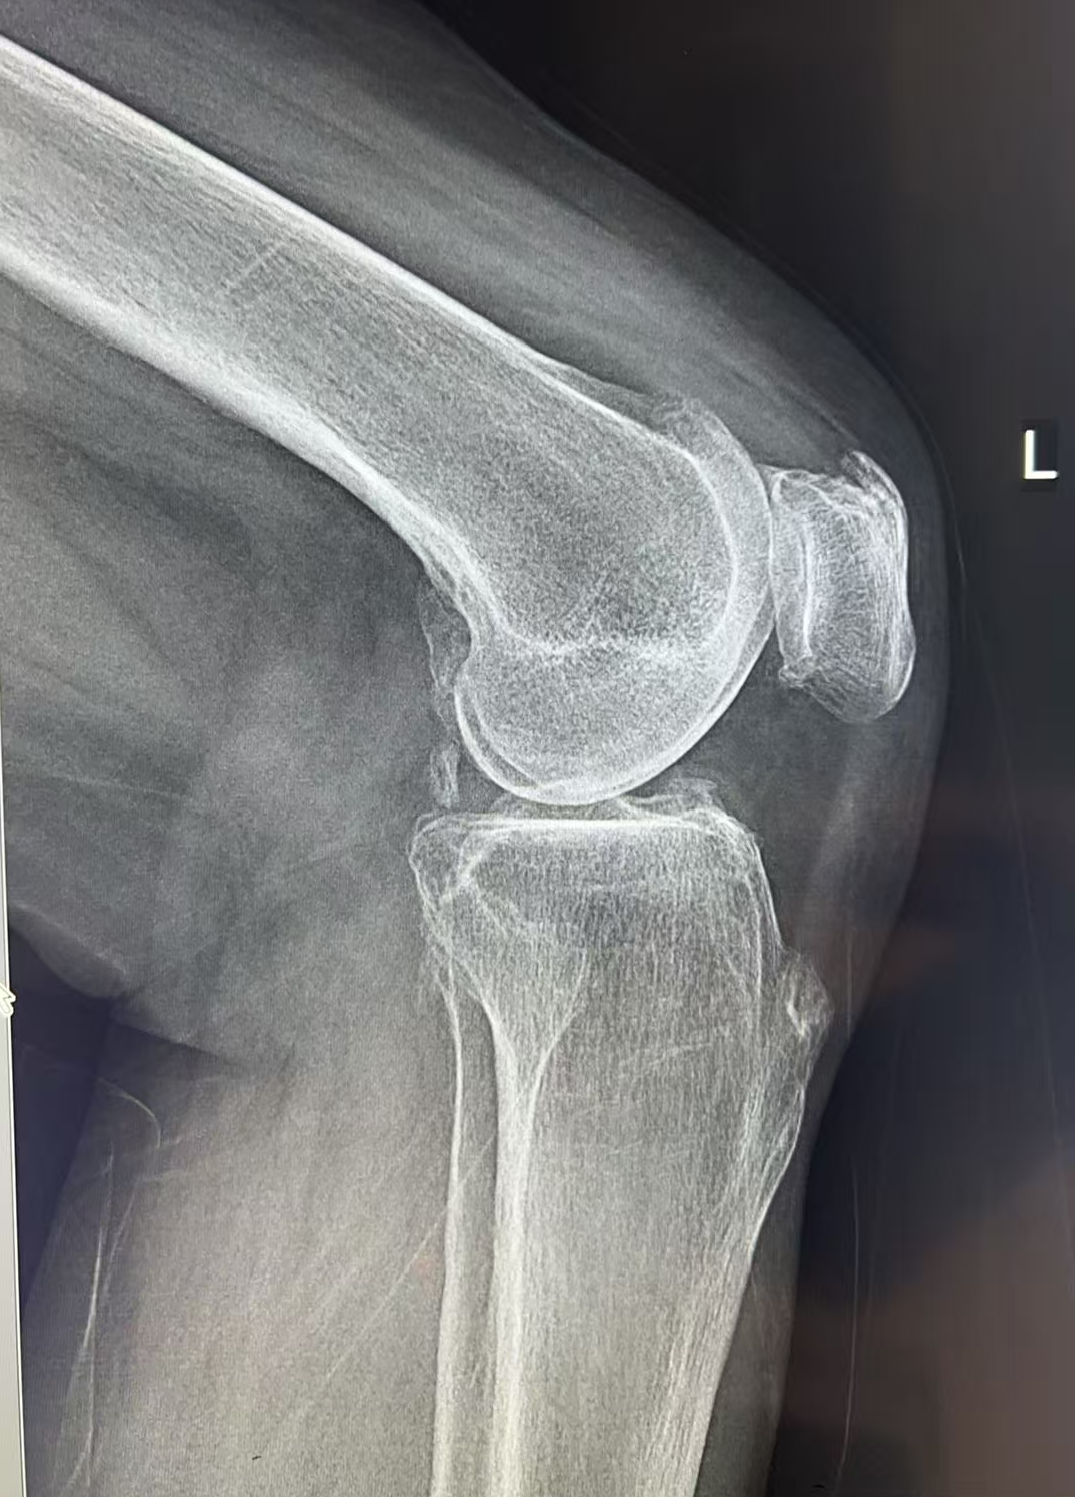

接诊她的是王歆峰主任,王主任耐心地听王阿婆讲了自己的情况,又仔细给她做了查体,还安排了详细的检查。最后确诊,王阿婆得的是 「左膝关节骨性关节炎」。

经过仔细评估,王歆峰主任决定给王阿婆做「左膝内侧单髁表面置换术」!这就是保膝治疗的一种,简单说,就是只修复膝盖磨损的那一部分,不用把整个膝盖关节换掉。手术很顺利。